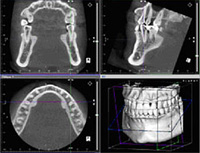

当院は、これまでに1,000本以上のインプラント埋入実績を誇ります。歯科用CTを駆使して骨の状態や位置を見ながら、さまざまな状況に対応する安心で確実な治療を提供します。

当院では歯科用CTを導入し、顎の神経の位置や骨の厚み、骨の質など、CTで得られる多くの情報をもとに治療計画を立てていきます。

口腔内の状態をしっかり確認後、CT画像撮影などによる十分な診査・診断を行います。

CT診断では様々な角度から骨の厚さや、神経・血管の位置などを確認します。